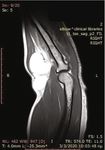

A CT and MRI with contrast demonstrated a well-encap-                    Figure 1: Preoperative view of the patient’s forearm.

sulated, solid multilobular lesion with lipoid content and the

presence of septa (Figures 2 and 3). The enhancement of the                 At present, the WHO Classification of Soft Tissue

septa demonstrated the rich vascularity of the lesion. There           Tumors classifies angiolipomas in the group of adipocytic

were no signs of infiltration of the surrounding tissues. The           tumors, the largest group of mesenchymal tumors (the same

dimensions of the lesion were 4:8 × 4:7 × 7:03 cm. The find-            as lipomas, liposarcomas, etc.) [8]. It is described as a benign

ings suggested a lipoma, but the imaging could not exclude             soft tissue tumor subdivided into infiltrative and noninfiltra-

a sarcomatous transformation due to the presence of septa              tive types. The rare infiltrative, nonencapsulated type typi-

and of the dishomogeneity of the signal’s density.                     cally involves deep soft tissues and is separated from the

Figure 2: CT scans.

Figure 3: MRI images (performed with a 1.5-Tesla unit): (a) axial T1-weighted image; (b) axial T1 fat suppression; (c) sagittal T1-weighted image.